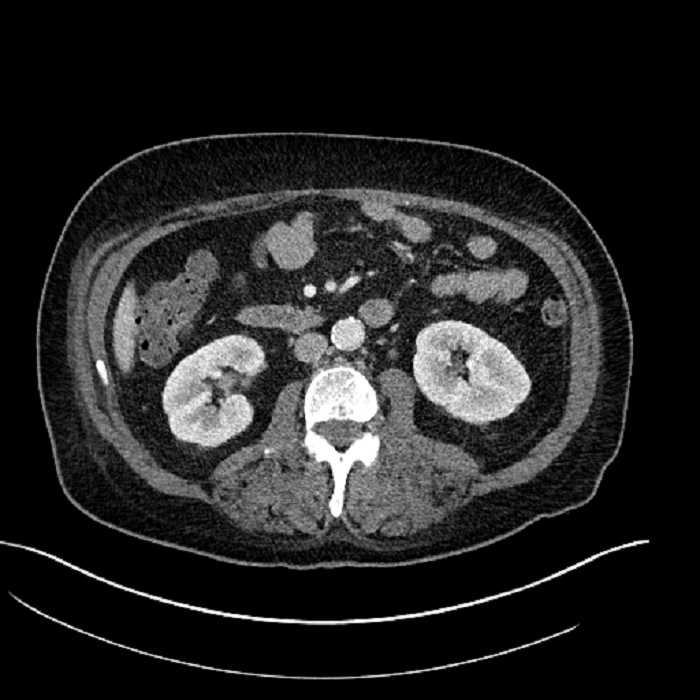

Age: 63

Sex: Male

Indication: Abdominal pain

• Large fluid density structure in hepatic segments 7 and 8 measuring 10 x 7 x 7 cm with internal septation and circumferential ill-defined low density compatible with edema

• Peripherally enhancing subcapsular collections along the anterior margin of the left hepatic lobe measuring 3 x 1 cm and 2 x 1 cm

• Clearly marginated fluid density structure in segment 7 and several other scattered tiny hypodensities, which likely represent cysts

• Hepatic abscess

Acute sigmoid diverticulitis complicated by a small contained perforation and a large abscess in the right hepatic lobe. Additional small subcapsular abscesses along the anterior margin of the left hepatic lobe.

• The classic CT imaging appearance is a double target sign with internal low density surrounded by an internal enhancing rim (capsule) and a low density external rim (edema)

Hepatic abscess showing the double target sign with low density internally surrounded by a thin inner enhancing rim (red arrow) and ill-defined outer low density rim (yellow arrow). Blue arrow indicates an internal septation. Red arrows: additional smaller subcapsular abscesses. Red arrow: focal contained perforation associated with diverticulitis.